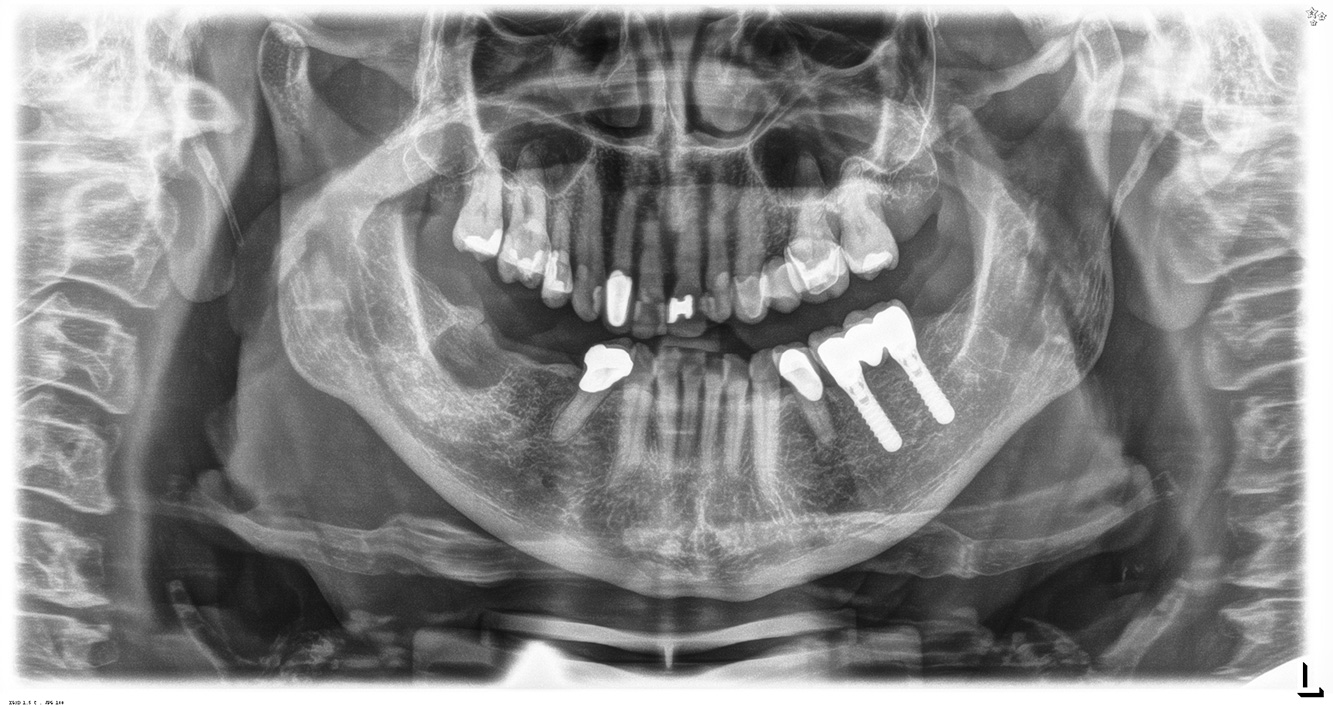

Die 68-jährige Patientin hat keine zahnmedizinisch relevanten allgemeingesundheitlichen Vorerkrankungen oder Medikation, auch aus dem Lebensstil ergibt sich kein besonderes Risiko. Die Patientin hat zwei Implantate (3. Quadrant, seit fünf Jahren) sowie eine parodontale Vorerkrankung (Parodontitis Stadium IV, Grad B) mit Zahnverlust. Derzeit zeigen sich stabile parodontale Verhältnisse. Für die Prophylaxesitzung ergeben sich vier Empfehlungen in den Bereichen Anamnese/Befund, Motivation/Instruktion, der Wahl der geeigneten Instrumente und für Resümee/Folgetermin.

Da die Patientin keine besonderen Risikofaktoren mit spezifischen zahnmedizinischen Auswirkungen hat, ist der aus der Mundgesundheit ermittelte Bedarf maßgebend. Hier ist einmal jährlich ein ausführlicher Parodontalstatus empfohlen. So kann rechtzeitig auf eine mögliche Progression der parodontalen Vorerkrankung oder die Entstehung einer Periimplantitis reagiert werden.

Aufgrund der Implantatsituation mit parodontaler Vorerkrankung hat die Patientin ein Entstehungsrisiko für eine Periimplantitis – empfohlen wird eine Wiedervorstellung im Intervall von drei bis vier Monaten.